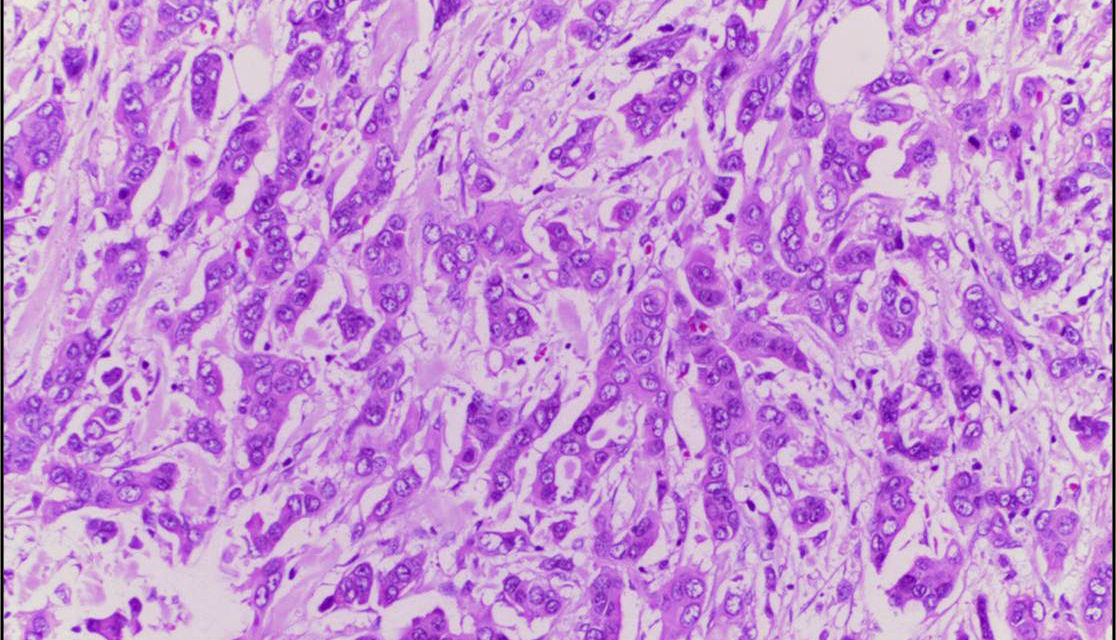

- Wikimedia Commons amb Llicència Creative Commons Attribution 4.0 International